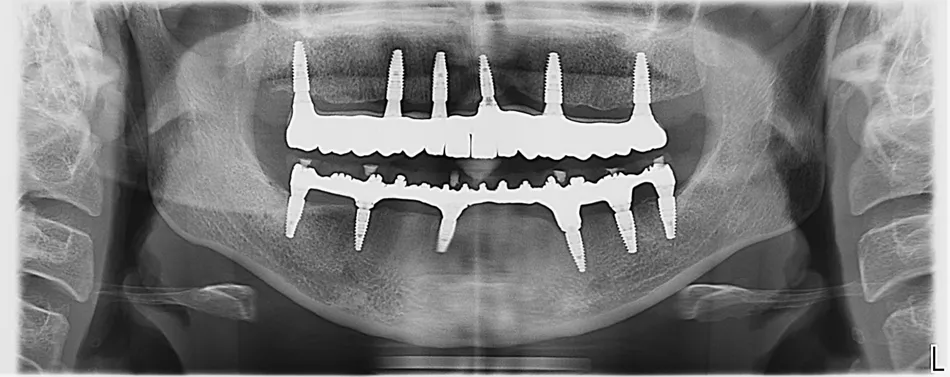

Иллюстрация 25

Ортопантомограмма спустя год после завершения реабилитации пациентки. (Илл. 25)